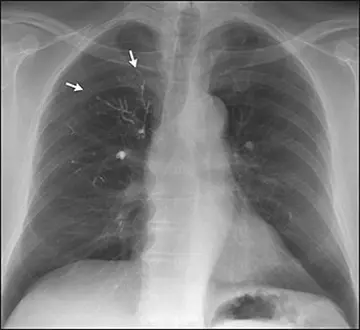

رادیولوژی - صفحه 3